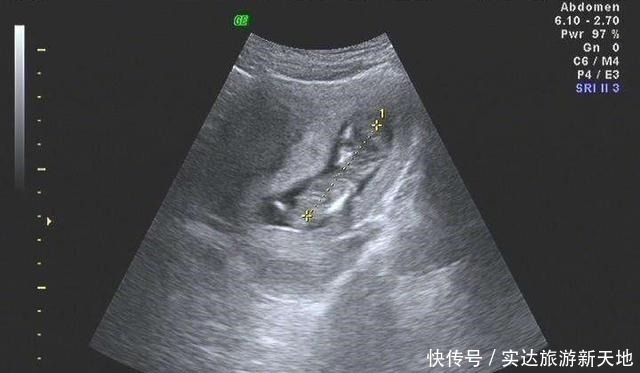

1、宝宝头臀长孕早期宝宝一般大约有5厘米长,在子宫内都是身体蜷缩的姿态,想要测量宝宝的长度是比较难的。所以大家一般会选择测量宝宝的头臀长。头臀长是指宝宝头部最顶端到宝宝臀部最底端的距离。正常的头臀长标准数据如下:孕期2个月:(3.27cm至4.14cm)孕期3个月:(4.3cm至5.29cm)孕期4个月:(5.47cm至6.59cm)孕期5个月:(6.78cm至8.02cm)具体测量孕周方法的公式:孕周期=CRL+6.5,假如,B超数据单的头臂径是6.03厘米,那么宝宝的孕周期是6.03+6.5=12.53周。